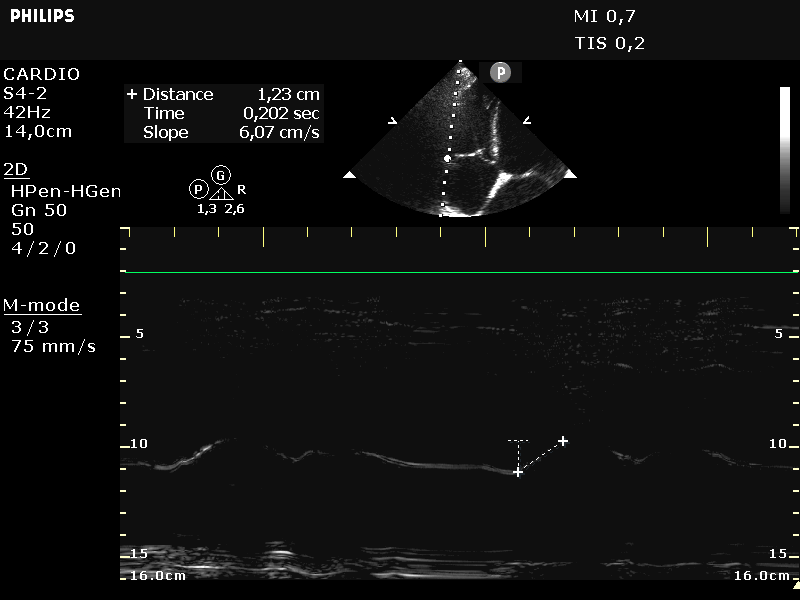

vena cava inferior in M-mode

Meting van diameter en mate van collaps

van vena cava inferior met de ademhaling